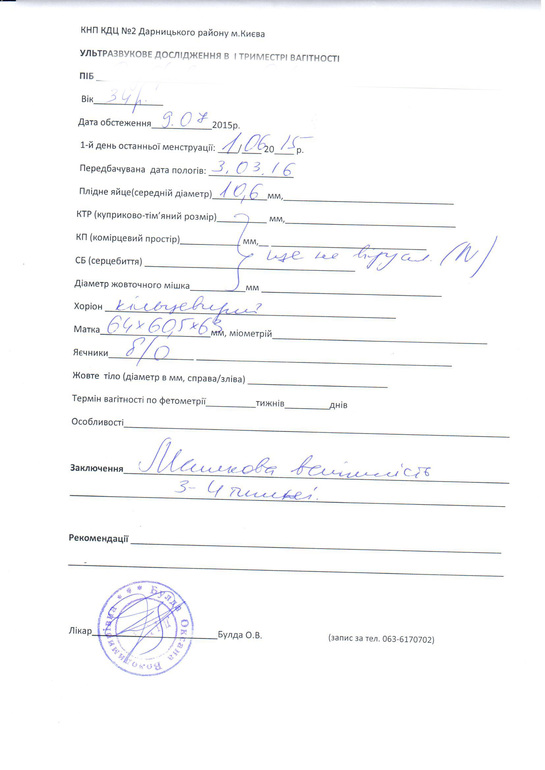

девочки от месячных у меня сейчас 5 недель и два дня ПЯ соответсвуетисроку 4-5 недель эмбрион и желточный мешочек пока не видно есть еще отслойка плодного яйца эндометрий 21 желтое тело 11. Девочуи у кого на 5 недели не видели эмбрилн и желточный мешочек чем все закончилось. А то я очень преживаю. Всем заранее спасибо.

5 недель не видно эмбрион и желточный мешочек

Всем привет! У меня ситуация, наверное, хуже всех! На 5 недели беременности мне сделали узи было все идеально-плодное яйцо, желточный мешок, эмбрион ещё не визуализировался, через несколько дней мне стало плохо, были коричневые выделения, пошла на узи-у меня отслойка, желточного мешочка нет, эмбриона по прежнему нет, сдала хгч-оно растёт, иду опять на узи, срок 5 недель и 5 дней-плодное яйцо выросло, отслойка также есть, эмбриона также нет, желточный мешочка также нет, врач настаивает на фармаборте, это моя первая беременность, не получалось долго, врачи ставили бесплодие и тут такое чудо и я должна его убить, собственноручно выпить эту таблетку для фармаборта…я обратилась к другому врачу, та уложила меня дома на сохранение назначила дюфастон и фолибер пить, и на сроке 7 недель прийти на узи, послушала ее, лежу дома не встаю, она сказала эмбриона не видно потому что он крошечный, но, я думаю, куда тогда делся желточный мешок? Девочки, может у кого-то что-то похожее было, поделитесь, пожалуйста🙏🏻

А желточный мешочек видно было. Знаю что рано. Хотела себя успокоить а получилось с точностью наоборот.

Всем огромное спасибо просто на узи узистка так это сказала что типа он должен быть а его нету я за мешочек.

Девочки всем огромное спасибо вы меня успокоили. А через неделю пойду на узи посмотреть что с отслойкой.